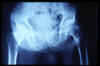

APR Fractura de pelvis